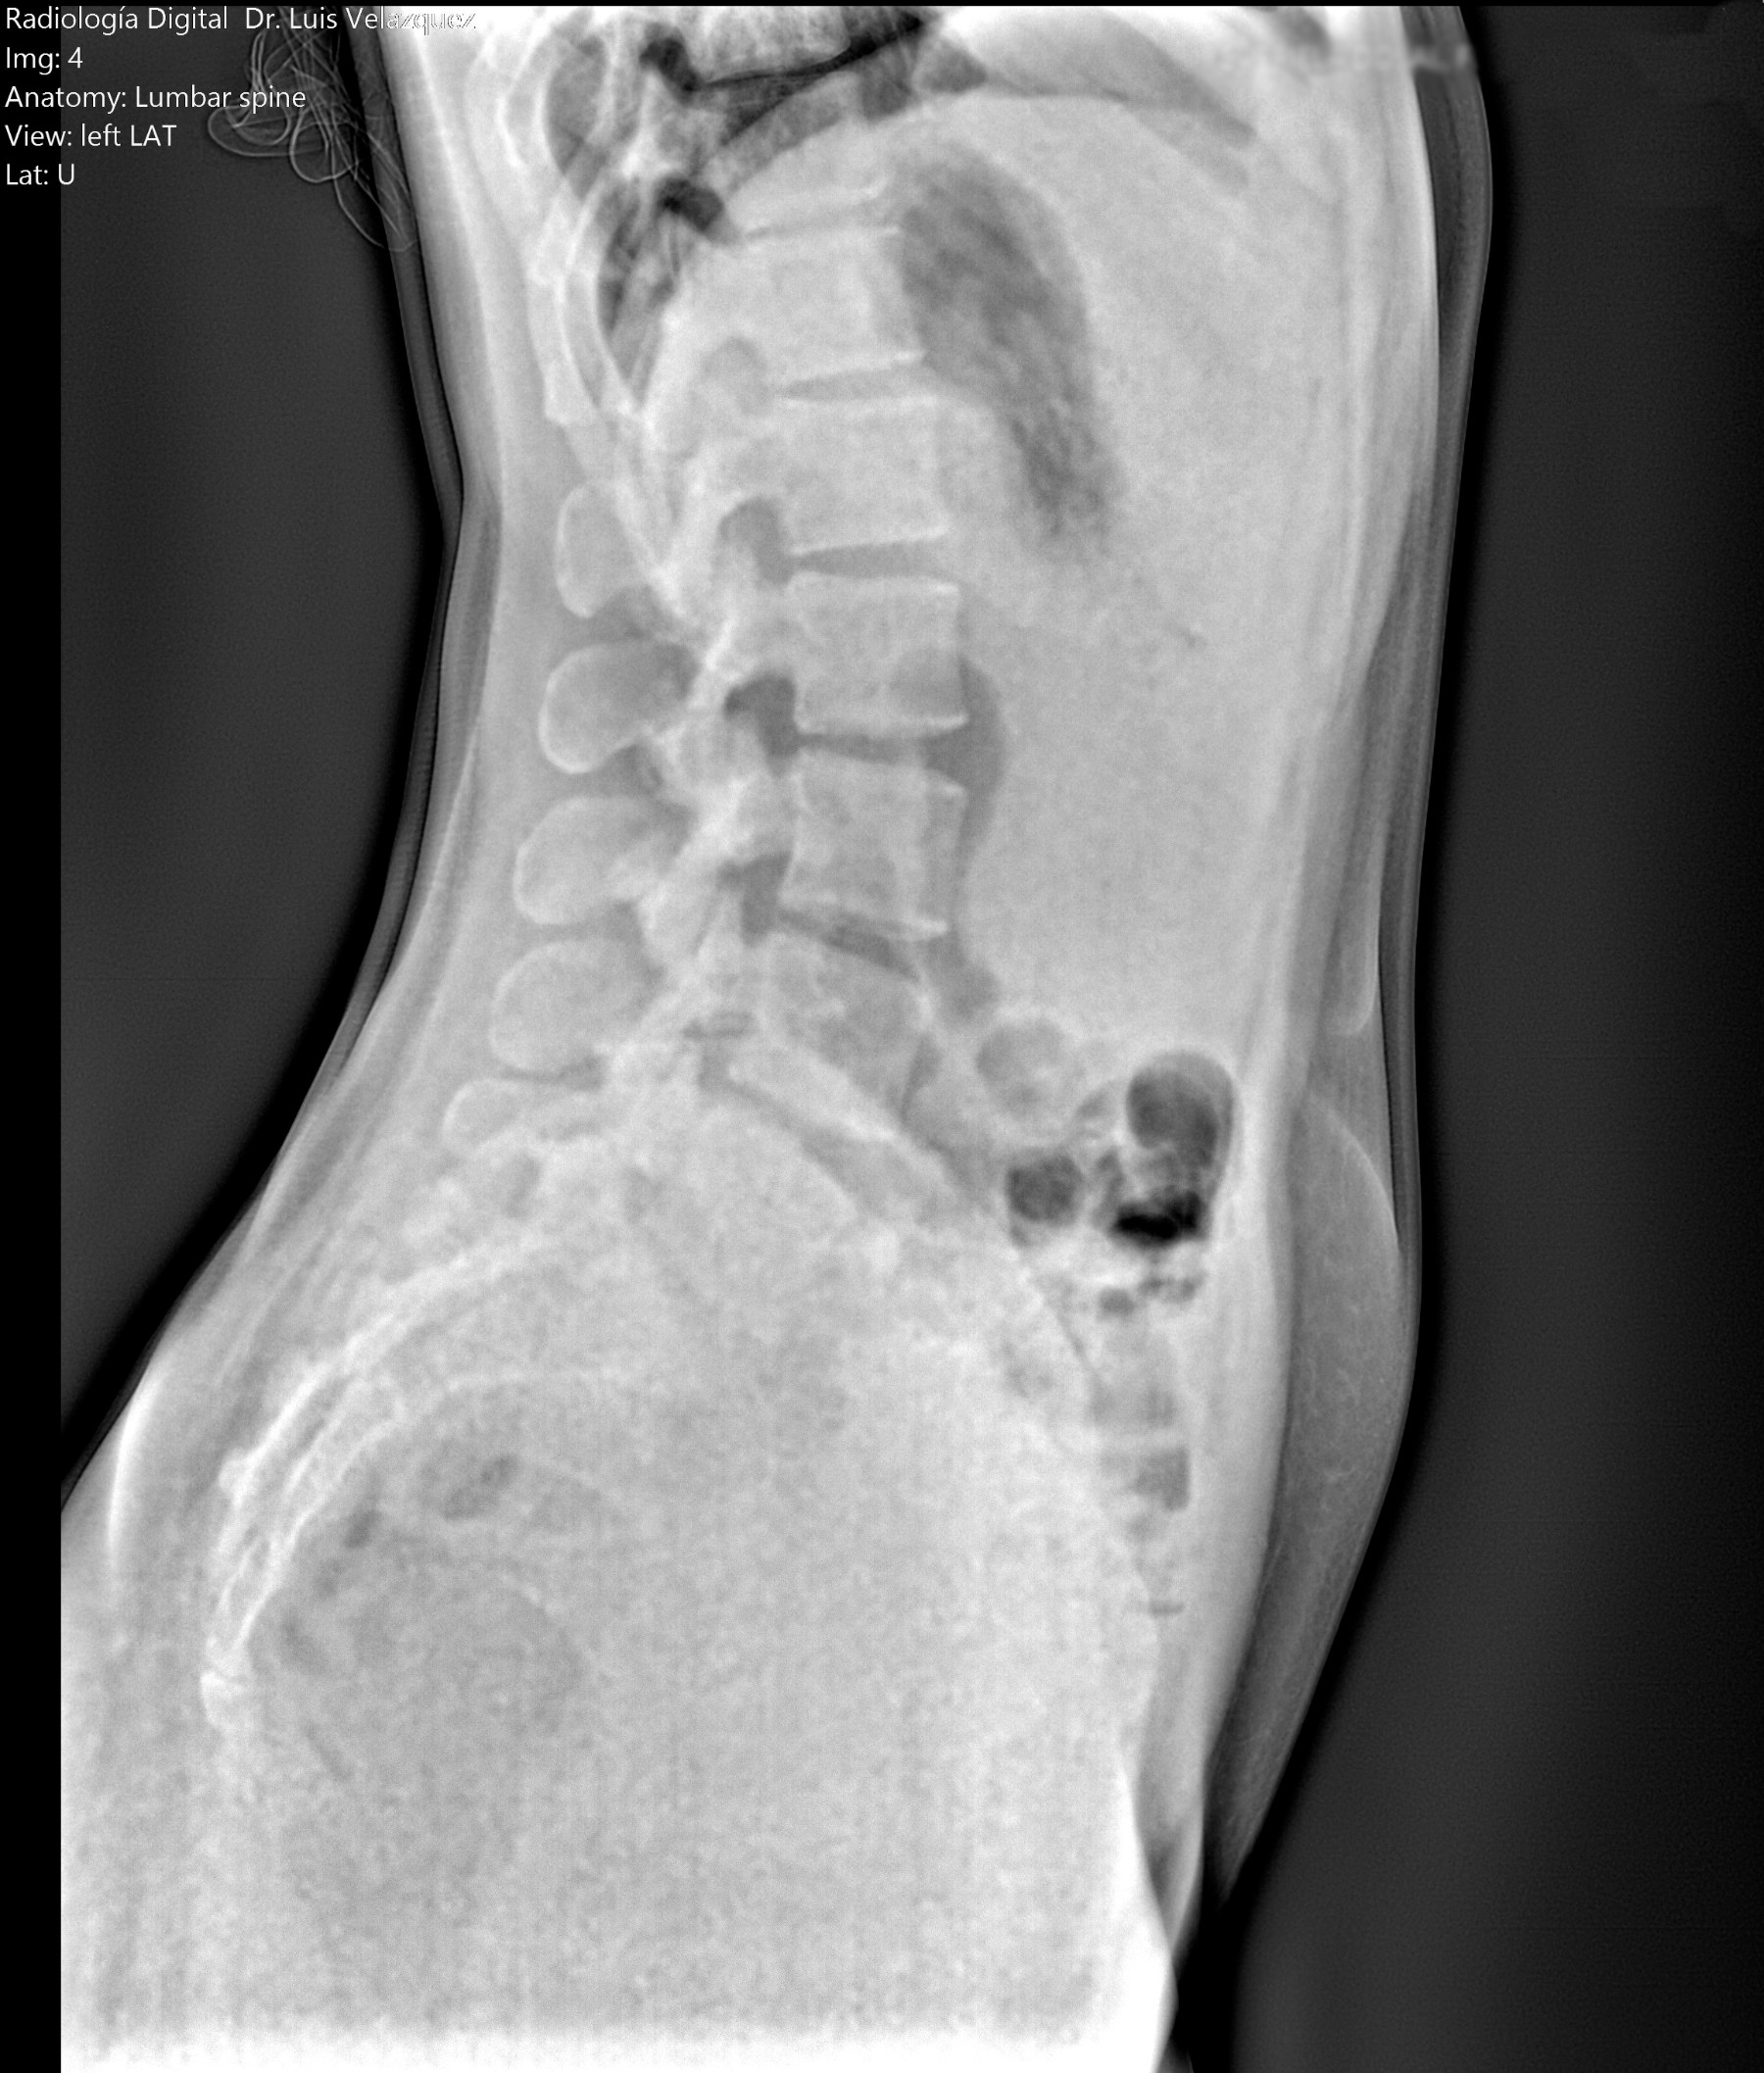

Cambios Térmicos en las Extremidades de Caballos,

Asociados a Golpes y su Evaluación por Termografía.

Los caballos de salto, en competencia, pueden derribar obstáculos y lastimarse. Si se golpean, no siempre claudican. Considerando al calor como un signo de inflamación, se evaluaron los cambios térmicos de 6 áreas de las extremidades torácicas y pelvianas de 23 caballos de salto en nivel de competencia de 1.05 a 1.60 m de altura, por medio de termografía durante 4 días de competencia (N=2208 áreas).